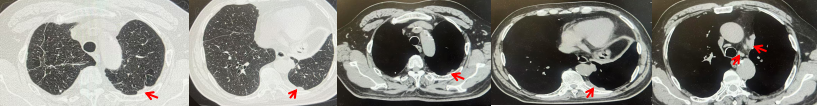

图4:该患者诊治经过

图8:该患者诊治经过